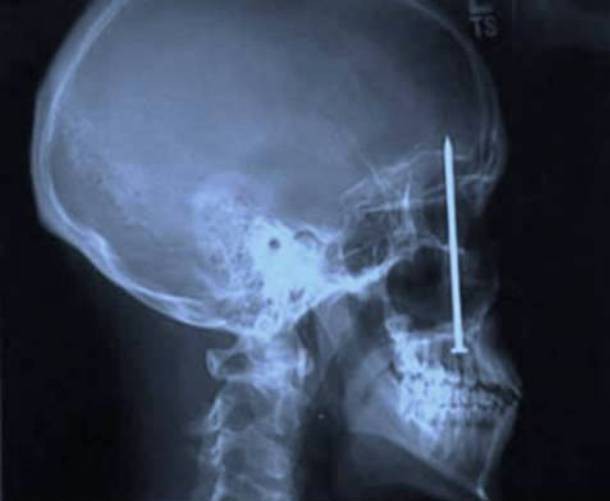

1. Cái này không phải là đau răng...

Vào thời điểm trước khi đi khám, Patrick Lawler vẫn cứ nghĩ rằng mình đang bị đau răng. Sau khi đi khám và chụp X-quang, anh đã có thể thở phào rằng hàm răng của mình vẫn ổn nhưng chẳng hiểu sao lại có một cái đinh nằm gọn gàng trong hộp sọ xuyên lên đến tận... não...